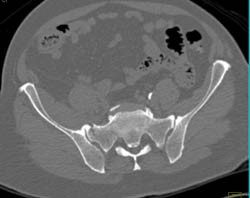

Cellulitis